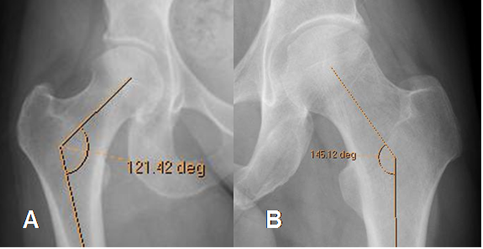

Mediciones importantes a la hora de valorar la patología de la cadera.

Fig 16. Angulo cervicodiafisiario normal.

Fig 18. Angulo de cubrimiento lateral normal.

Rx AP de cadera.